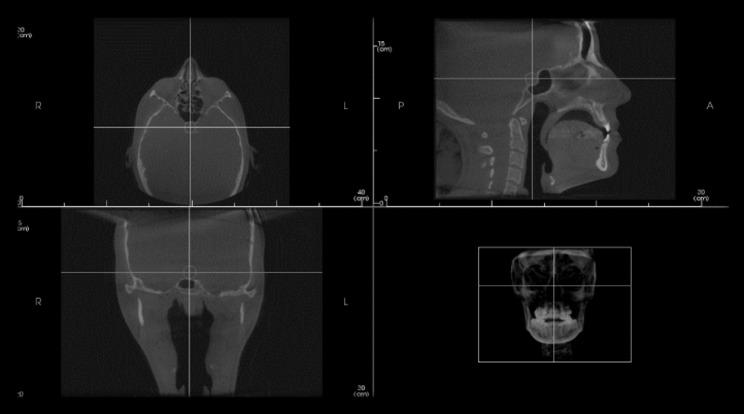

A total of 52 cone beam computed tomographic (CBCT) images were selected with an age range of 18-30 years. Group I comprised 26 patients previously diagnosed with transverse maxillary deficiency, while group II comprised 26 patients with normal transverse skeletal relationships. The length, depth and diameter of the ST were measured by two observers, the shape was evaluated as round, oval or flat and sellar bridging was calculated in each case. An Independent t-test was used to compare between the sellar dimensions in both groups. For assessment of bridging percentage Chi square test was used.

共选择 52 例锥形束 CT(CBCT)图像,年龄范围为 18-30 岁。I 组包括 26 例经诊断为横向上颌骨不足的患者,II 组包括 26 例横向骨骼关系正常的患者。由两位观察者测量鞍区的长度、深度和直径,评估鞍区的形状为圆形、椭圆形或扁平形,并计算每个病例的鞍区桥连情况。使用独立 t 检验比较两组之间的鞍区尺寸。使用卡方检验评估桥连百分比。